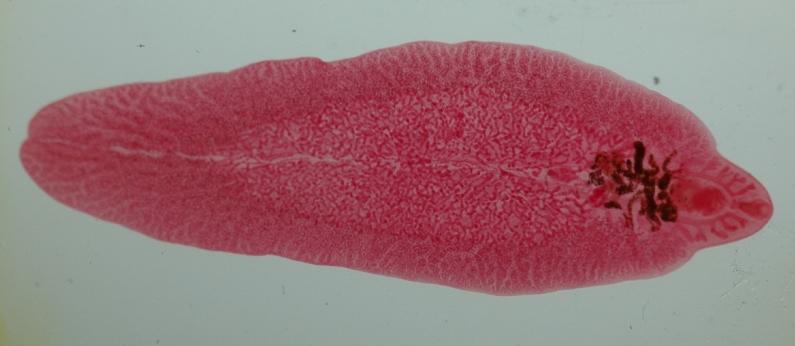

Сосальщики (трематоды)- черви в организме человека

Черви-гельминты. Сосальщики это вид червей, паразитирующих в любых органах и тканях. Они питаются эпителиальными клетками. Достигают в длину до 1,5 м. Тело по форме напоминает листок.

Путь заражения употребление рыбы, морепродуктов в сыром виде, либо после недостаточной термической обработки.

К данному виду относятся: печеночный сосальщик: червь длиной 7-20 мм. Паразитирует в печени, а также жёлчных протоках.

- Печёночный сосальщик поселяется в человеке через употребление в пищу рыбы, ранее им пораженной. Этот червь наносит вред желчному пузырю и кишечнику. Признаки инвазии сосальщиком: аллергия и тошнота, боли в животе и спазмы, болят также суставы, поднимается высокая температура. Если болезнь перешла в хроническую форму, то следующим этапом возможен гепатит. Более страшные последствия инвазии печеночным сосальщиком цирроз и рак. Если этот гельминт уничтожен и удален, причиненный им вред будет вполне ощутимым, остается воспаление печени.